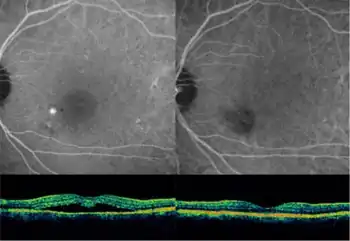

Optical coherence tomography imaging of central serous retinopathy

The diagnosis usually starts with a dilated examination of the retina, followed with confirmation by optical coherence tomography and fluorescein angiography. The angiography test will usually show one or more fluorescent spots with fluid leakage. In 10%-15% of the cases these will appear in a "classic" smokestack shape. Differential diagnosis should be immediately performed to rule out retinal detachment, which is a medical emergency. A clinical record should be taken to keep a timeline of the detachment. The affected eye will sometimes exhibit a refractive spectacle prescription that is more far-sighted than the fellow eye due to the decreased focal length caused by the raising of the retina.